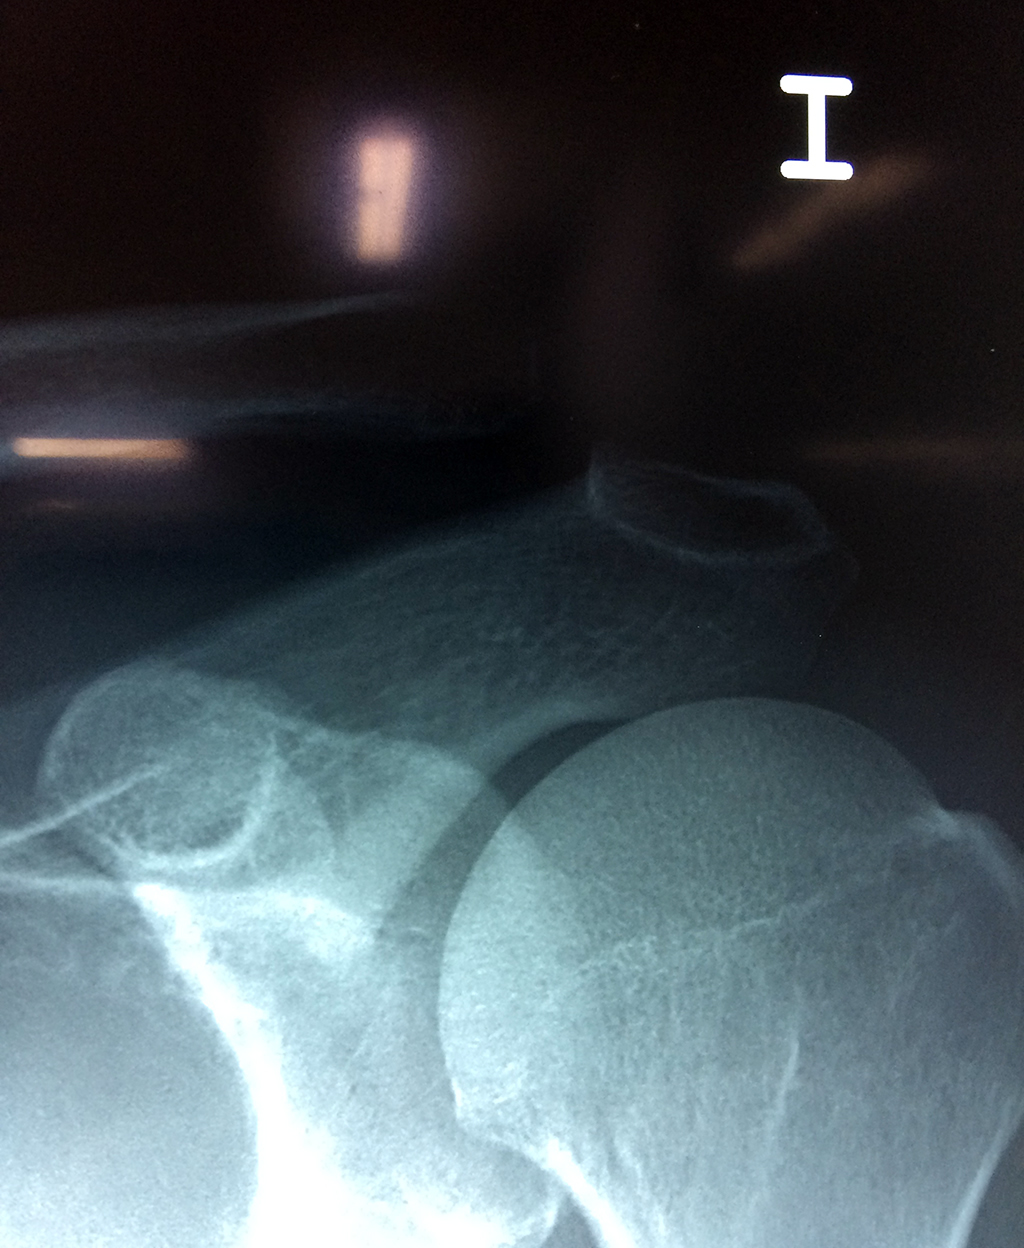

La clavícula es un hueso largo, con forma de "S" itálica, situado en la parte anterosuperior del tórax. Junto con la escápula forman la cintura escapular. Se puede palpar por toda su longitud y se extiende del esternón al acromion de la escápula, siguiendo una dirección oblicua lateral y posterior.